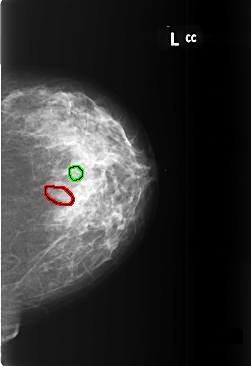

B_3400_1.LEFT_CC

FILE: B_3400_1.LEFT_CC.OVERLAY

TOTAL_ABNORMALITIES 2

ABNORMALITY 1

LESION_TYPE CALCIFICATION TYPE PLEOMORPHIC DISTRIBUTION SEGMENTAL

ASSESSMENT 4

SUBTLETY 3

PATHOLOGY BENIGN

TOTAL_OUTLINES 1

BOUNDARY

ABNORMALITY 2